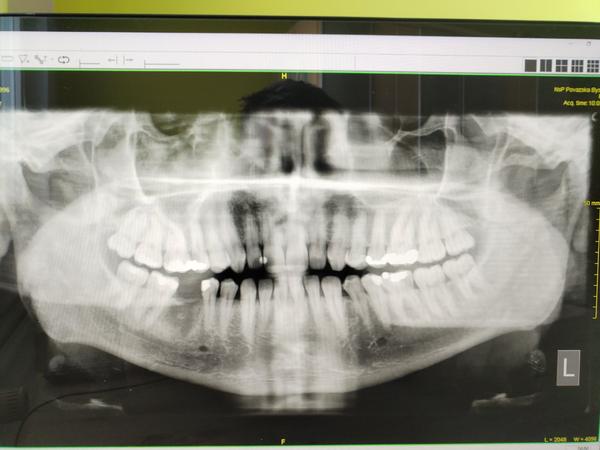

Môže niekto zhodnotiť moju OPG snímku?

Ahojte je tu niekto kto vie zhodnotiť opg snímku prosím ? Ak áno hodim ju sem ďakujem

Kto vie zhodnotiť tento zubný RTG?